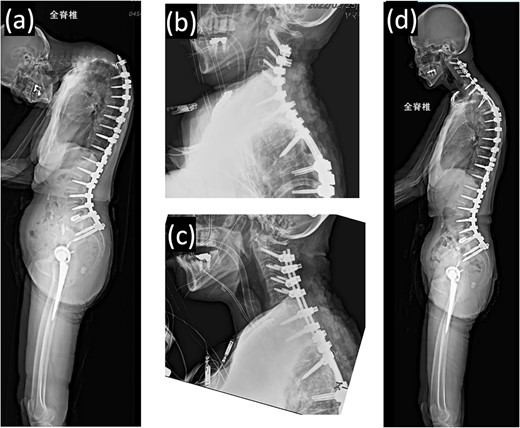

(a) Standing whole-spine radiographs 16 months after the first surgery, showing features of dropped head syndrome associated with proximal junctional failure; lateral radiographs immediately after (b) the second and (c) third surgeries; (d) standing whole-spine radiographs 16 months after the third surgery.

On postoperative Day 1, she resumed eating and drinking, but with delayed swallowing time. The wound drain was removed on postoperative Day 2, and walking exercises were initiated. Though no specific issues were noted, she exhibited signs of delirium, unclear responses, and occasional snoring-like breathing. However, on postoperative Day 6, a nurse found her bedridden, with a pale face and eyes open, drooling and snoring. The patient’s oxygen saturation was 55%; when the bed was flattened and the airway was suctioned, consciousness was restored and oxygenation improved in ~20 s. The diagnosis was obstructive dyspnea, supported by the persistence of snoring after resuming breathing. Neurological symptoms had not worsened, and intracranial lesions or cardiovascular events were deemed unlikely based on computed tomography (CT) scans, electrocardiograms, and blood test results. The rapid increase in the C2–7 angle from −15° before the second operation to 32° postoperatively led to the conclusion that a decrease in the O-C2 angle was associated with occlusive dyspnea. Emergency surgery was performed to re-fixate the cervical spine, reducing kyphosis (Fig. 2c). Postoperatively, the patient was managed on a ventilator and extubated on the second postoperative day. Sixteen months later, she experienced no further dyspnea (Fig. 2d and 3b).

Lateral view of neck posture (a) before and (b) after the third surgery.